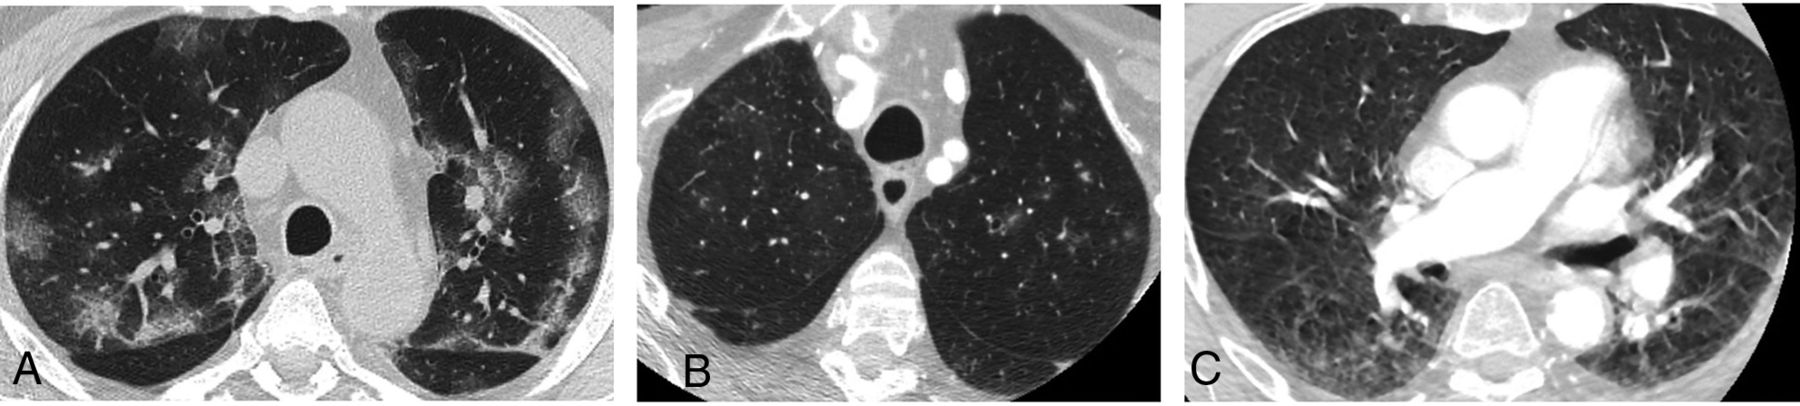

We observed apical GGO in 22.2% (50/225) of patients in 2020. In 2020, when using the descriptive COVID-19 CT grading system, 28.0% (14/50) of those with GGO were rated as COVID-19-typical; 24.0% (12/50), indeterminate; and 48.0% (24/50), non-COVID-19; all features were more common than in 2019 (P < .001) (Fig 1).

A, There are multiple, bilateral, focal, peripheral-predominant areas of ground-glass opacification, commonly seen in patients with COVID-19 pulmonary infection. B, There are multiple, focal 5- to 6-mm nodules with surrounding ground-glass change in the left upper lobe. This is an indeterminate COVID-19 appearance and would be more suggestive of atypical or fungal infection. C, There is bilateral ground-glass opacification posteriorly, more on the right, consistent with dependent change. This is a characteristic appearance, not associated with COVID-19, and classically disappears in the prone position. There is also a general hazy appearance not seen in A and B, which does not represent abnormal lung and is artifactual due to movement.